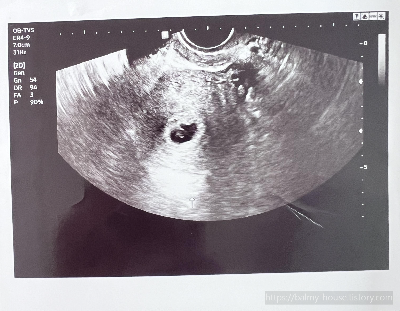

임신 6주 차 (6w 5d)

1월 11일

심장 소리 확인

아기집이 확인되고 일주일 만에 심장소리를 듣기 위해 내원했다.

일주일 만에 심장이 뛴다고?

심장소리는 132 bpm으로 아주 정상적으로 뛰고 있는 것이 확인되었다.